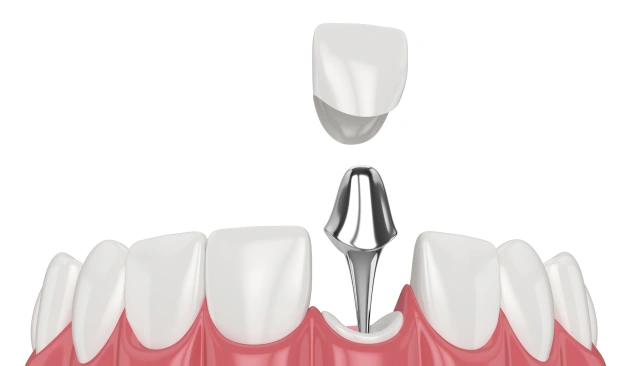

Post & Core / Build-Up (if tooth structure is weak)

Strengthens severely damaged teeth before crown placement.

*Price varies based on material used.